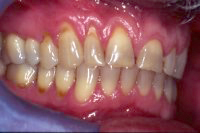

Die Abb. 1 bis 4 sollen als anschauliche Beispiele für gesunde und kranke Fundamente dienen.

Ein 31 Jahre alter Patient zeigt einen starke Zahnfleisch-Rückgang im Oberkiefer (Abb. 1 und 3) und wir beschliessen, diese Rezessionen zu behandeln.

Der Erfolg der Behandlung ist deutlich in den Abb. 2 und 4 zu sehen. Sehr augenfällig konnte die Situation um den Eckzahn im linken Oberkiefer verbessert werden (vergleiche dazu Abb. 3 vorher und Abb. 4 nachher).